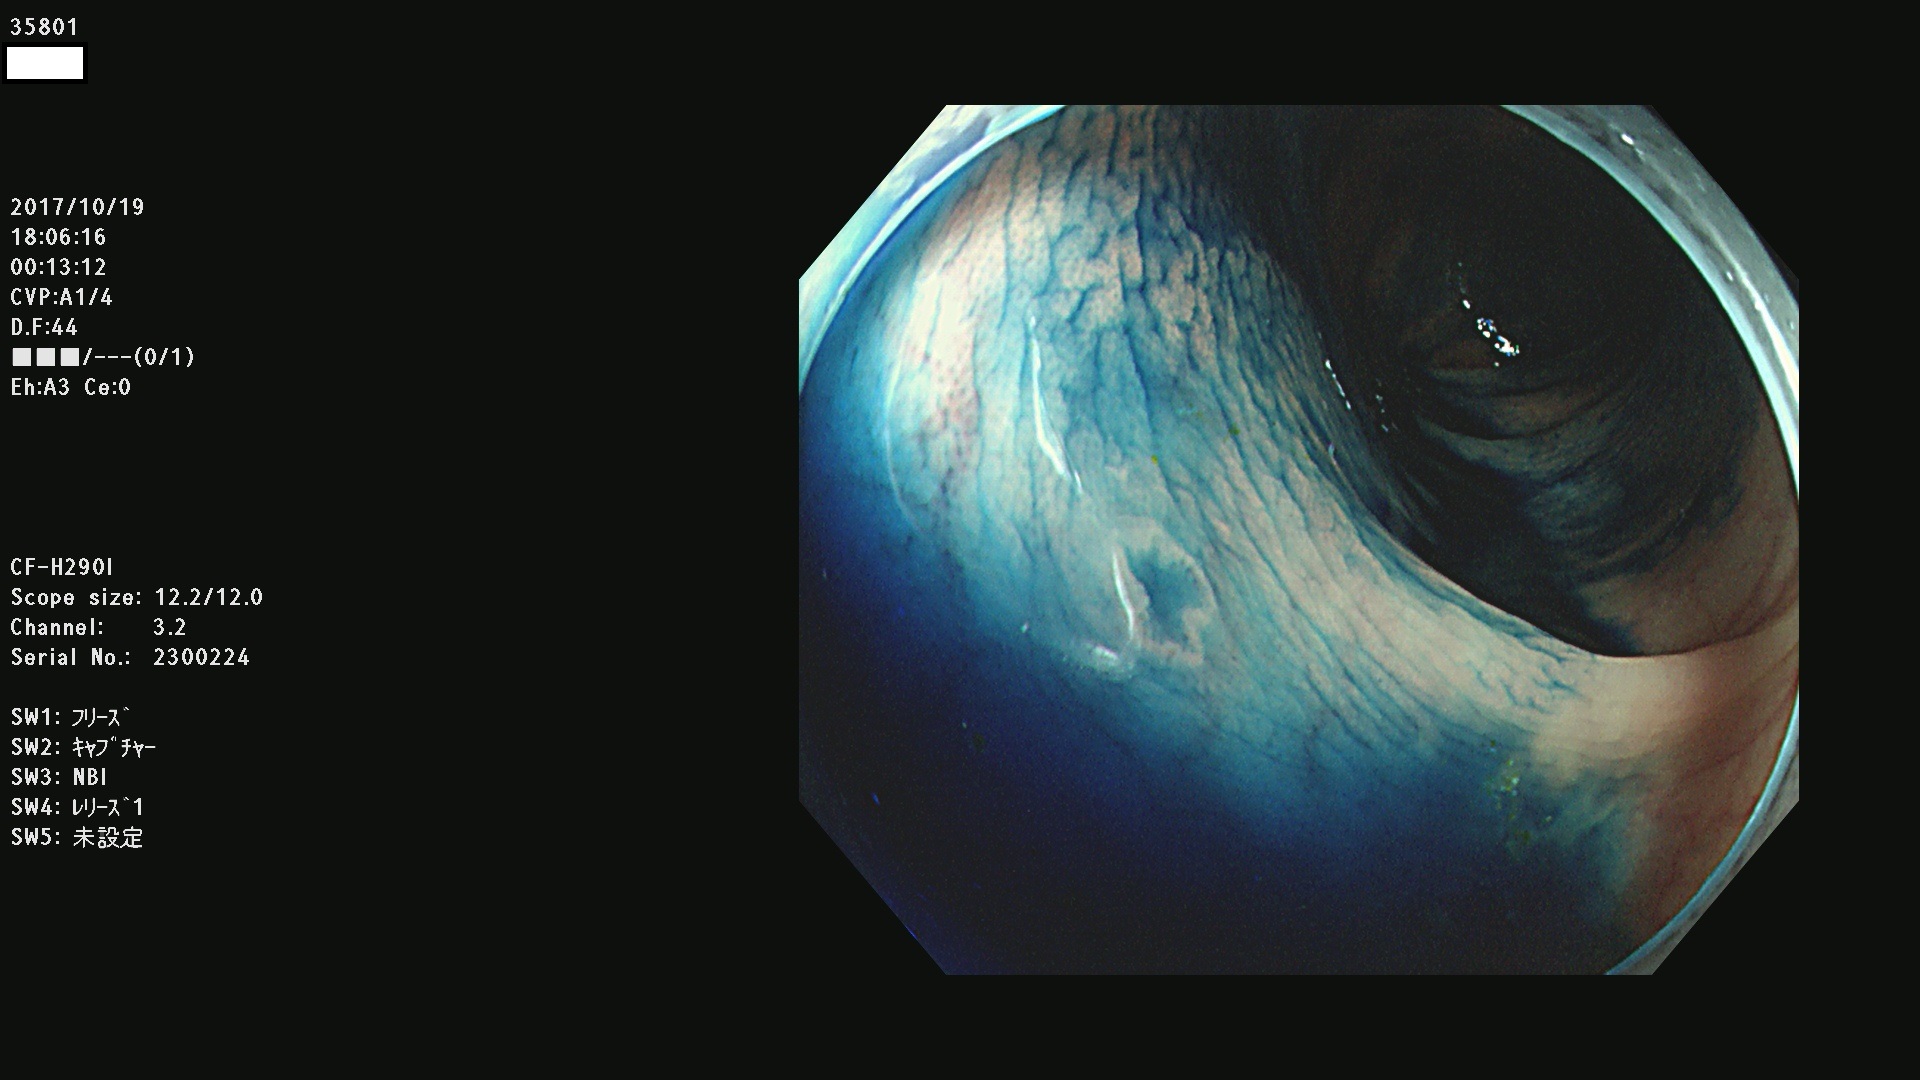

35801 35802 35806 35808 35816 35820 35821 35826 35828 35830(SSA/Pのみ) 35833 35834 35835 35837 35838 35840 35841 35843 35847 35852 35855 35857 35859 35863 35864 35865 35866 35867 35869(SSA/Pのみ) 35872 35873 35875 35878 35880 35882 35885 35886 35888 35890 35893 35895 35896 35897 35898

発見困難で危険性の高い平坦型病変(上記100名より抽出)